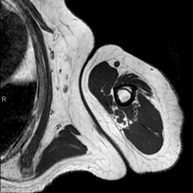

- Hip MRI

Examination for the study of injuries to tendons, muscles and hip joints. Enables early detection of hip osteoarthritis. It is very useful for detecting bursitis and dynamic osteopathy of the pubis, which is common in athletes. It lasts approximately 20 minutes. It is a radiation-free procedure.

- Hip MRI arthrography

Examination to study injuries to small anatomical structures of the joint that are commonly injured in patients suffering from dislocation or impingement (narrowing space). Prior to the examination, a contrast fluid is injected into the joint, guided by X-ray imaging. The total duration of the two procedures is 50 minutes.